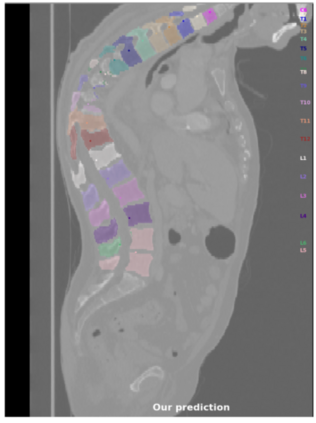

Vertebrae localization, segmentation and identification in CT images is key to numerous clinical applications. While deep learning strategies have brought to this field significant improvements over recent years, transitional and pathological vertebrae are still plaguing most existing approaches as a consequence of their poor representation in training datasets. Alternatively, proposed non-learning based methods take benefit of prior knowledge to handle such particular cases. In this work we propose to combine both strategies. To this purpose we introduce an iterative cycle in which individual vertebrae are recursively localized, segmented and identified using deep-networks, while anatomic consistency is enforced using statistical priors. In this strategy, the transitional vertebrae identification is handled by encoding their configurations in a graphical model that aggregates local deep-network predictions into an anatomically consistent final result. Our approach achieves state-of-the-art results on the VerSe20 challenge benchmark, and outperforms all methods on transitional vertebrae as well as the generalization to the VerSe19 challenge benchmark. Furthermore, our method can detect and report inconsistent spine regions that do not satisfy the anatomic consistency priors. Our code and model are openly available for research purposes.